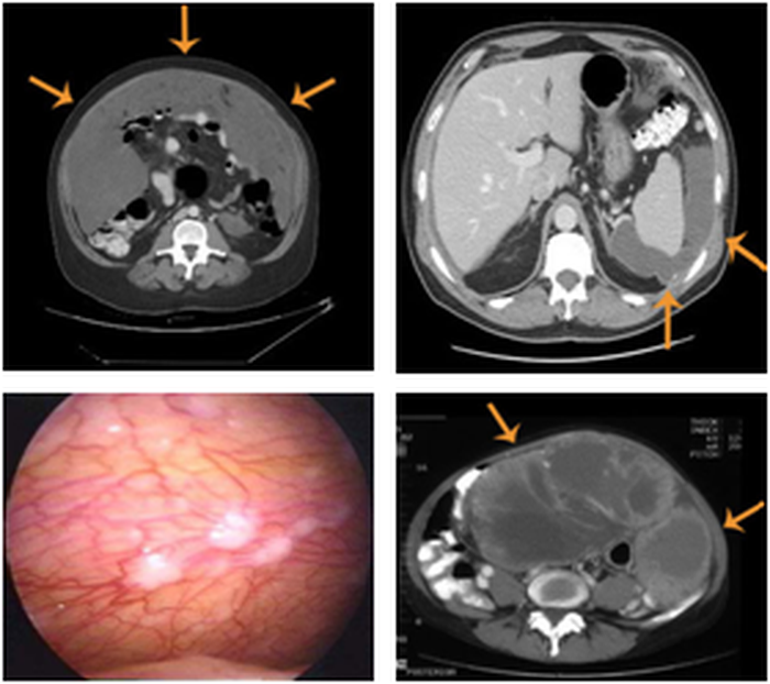

Karın içi kanserlerinin tedavisine başlamadan önce kanserin hangi organdan hangi sistemden kaynaklandığını bilmek gerekir. Karın zarı kanserleri karın zarından başlasın ya da başladığı organdan karın zarına ulaşsın cerrahiye eklenen sıcak kemoterapi hastalar için son 30 yıldır bir tedavi seçeneğidir ve gelişmiş ülkelerde modern tıbbın sunduğu bu hizmet cerrahi ile sıcak kemoterapinin birlikte uygulandığı kompleks işlemler ülkemizde. Ama hastalar genellikle geç evrede yakalanır. Kalp akciğerler ve karın bölgesindeki organları çevreleyen zardan kaynaklanan bir hastalıktır.

Karın zarı kanserinin nasıl oluştuğuna dair bilgi veren canbay karın zarı karın içindeki tüm organları kaplayan ince bir zardır. Bu organlar mide ince ve kalın bağırsaklar over yumurtalıklar apandisit gibi organlardan başlayan kanserler organın dış tabakasına ulaştığında karın zarı kanseri denilmektedir. Bu yöntemler hastaların yaşam kalitelerini yükseltirken aynı zamanda yaşam sürelerini uzatıyor ve bir grup hastada kür sağlıyor. Dünyada bir çok merkezde bununla ilgili koruyucu önlemler geliştirilmiştir.

Bu hastaların tedavisinde periton zarı tamamen soyulup çıkarılmaktadır. Cerrah ulaşılabilen tüm tümörleri cerrahi yolla veya koterizasyonla yok eder. Bu durumda kimyasal tedavi şarttır. Karın içi tümörlere sıcak kuşatma i̇leri evre karın içi kanserler olarak tanımladığımız peritona karın içi zarı yayılmış kanserlerin tedavisinde hi̇pek ve pi̇pak gibi karın içi kemoterapi yöntemlerine başvuruluyor.